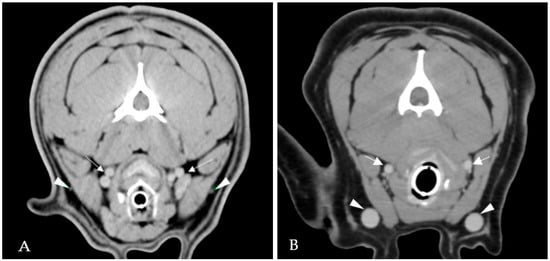

2.3. Case 3